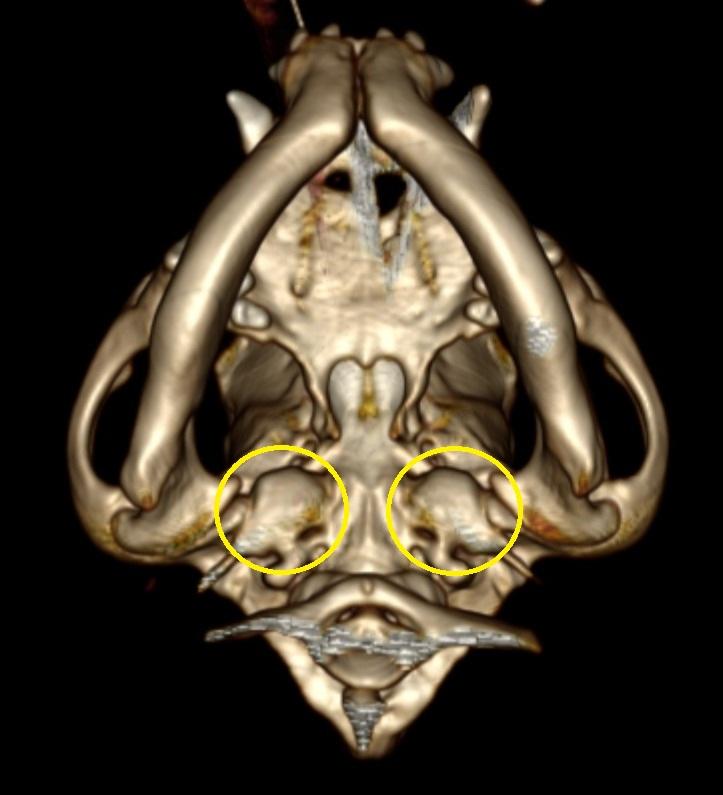

CT検査では、正常な鼓室胞は空気で満たされているので左画像のように黒く映ります。

一方、本症例では液体や軟部組織で鼓室胞内が満たされていることがわかります。

真珠腫 (cholesteatoma)は、短頭種に好発する疾患であり、そのほとんどは慢性外耳炎に続発します。